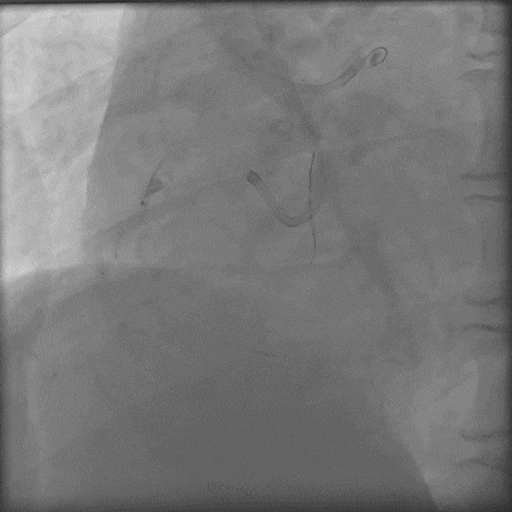

Corsair微导管耐心旋转通过病变;

最终结果满意。